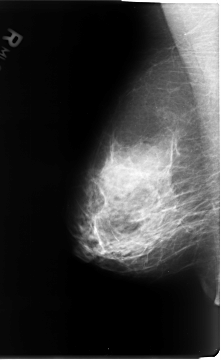

B_3072_1.LEFT_MLO

LEFT_MLO LINES 4656 PIXELS_PER_LINE 3016 BITS_PER_PIXEL 12 RESOLUTION 50 OVERLAY